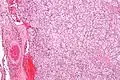

| Micrograph of a carotid body tumor (a type of paraganglioma). | |

On microscopic inspection, the tumor cells are readily recognized. Individual tumor cells are polygonal to oval and are arranged in distinctive cell balls, called Zellballen.[8] These cell balls are separated by fibrovascular stroma and surrounded by sustentacular cells.

Micrograph of a carotid body tumor